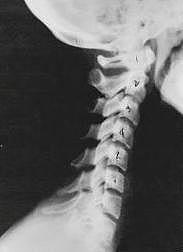

Phase One Subluxation Degeneration is seen in subluxations that have been present for up to twenty years. This phase is characterized with a loss or change in the normal curve in the spine. On this example you can see that the normal forward (lordotic) curve is lost. This spine even has developed a reverse curve in the neck. The disc spaces have also begun to exhibit a slight change in shape. One good point is that the bodies of each of the vertebrae (the square part in front) still exhibits clean clear borders. Segmental motion may be abnormal but overall motion is probably not affected. Chiropractic reconstructive care for a phase one can take from 6 to 18 months. More than 80% of people with Phase One Subluxation Degeneration have no pain. Therefore, if left uncorrected, phase one continues to progress with time until it eventually reaches the next phase.